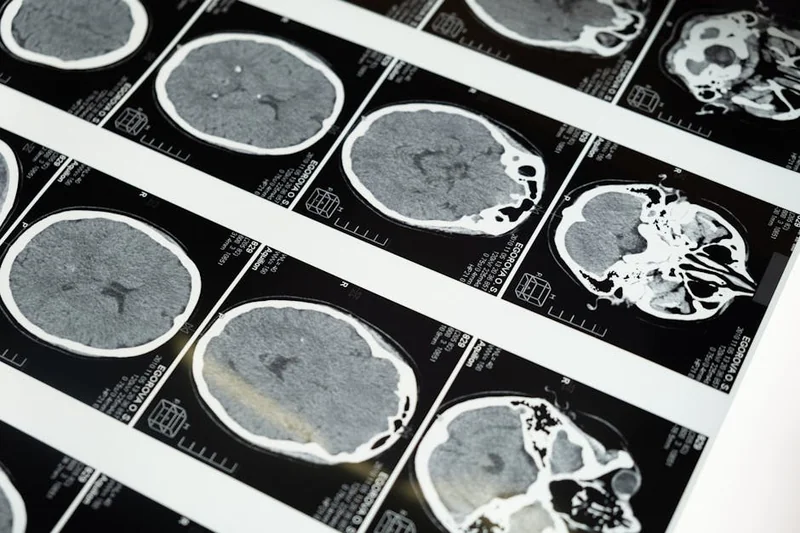

임사체험은 생리적으로 여러 가지 반응을 일으킵니다. 연구에 따르면, 임사상태에서 뇌의 특정 영역들이 비정상적으로 활성화되며, 이 과정에서 신경전달물질의 방출이 증가하게 됩니다. 특히, 감마파와 같은 고주파 뇌파가 두드러지게 나타납니다. 이는 뇌의 다양한 부분이 동시에 활성화되면서 발생하는 현상으로, 자아의 경계가 흐려지고, 더욱 높은 수준의 인식을 경험하게 됩니다.

임사체험 동안 뇌파의 변화는 의식의 깊이를 확장시키는 역할을 합니다. 특히 감마파의 급증은 뇌가 더 높은 차원의 인식을 가능하게 하며, 이는 결국 삶과 죽음의 경계를 넘는 경험으로 이어집니다. 뇌의 각 영역 간의 연결이 강화되면서, 인간은 하나의 통합된 경험을 하게 됩니다.

임사체험의 뇌파 분석

임사체험 동안의 뇌파를 분석한 연구들은 과학적으로 많은 흥미로운 결과를 제시했습니다. 많은 연구자들은 감마파의 활성화가 감정과 의식의 통합을 보여준다고 주장합니다. 이러한 변화는 경험자의 사고방식에 깊은 영향을 미치며, 새로운 인식의 지평을 열어줍니다.